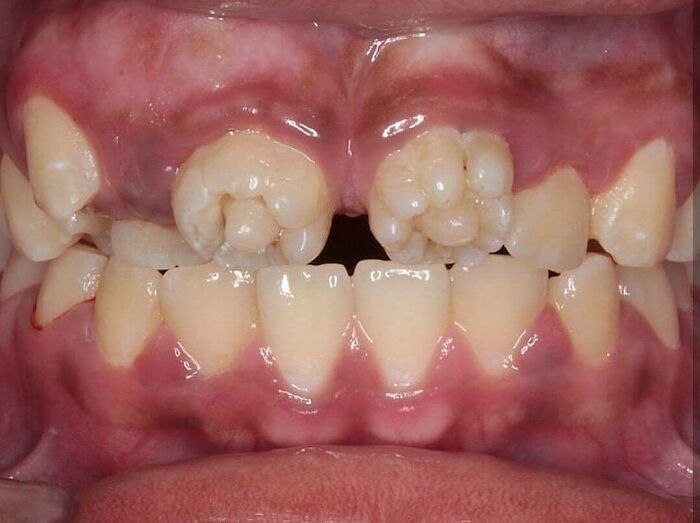

Mulberry molars are a dental condition usually associated with congenital syphilis, characterized by multiple rounded rudimentary enamel cusps on the permanent first molars. Mulberry molars are physically defective permanent molars. The deformity is caused by congenital syphilis. This type of abnormality is characterized by dwarfed molars with cusps covered with globular enamel growths. These teeth are functional but can be cosmetically fixed with crowns, bridges, or implants.

Just above the gum line, the mulberry molar looks normal. A deformity becomes apparent towards the cusp or top grinding surface of the tooth. Here, the size of the mulberry molar is diminished in all aspects, creating a stumpy version of a conventional molar. The cause of the molar atrophy is thought to be enamel hypoplasia, or a deficiency in tooth enamel. The underlying dentin and pulp of the tooth is normal, but the enamel covering or molar sheath is thin and deformed, creating a smaller version of a typical tooth.

The grinding surface of a mulberry molar is also corrupted. Normally, the grinding surface of a molar has a pit and is surrounded by a circular ridge at the top of the tooth, which is used for grinding. The cusp deformity of the mulberry molar is characterized by an extremely shallow or completely absent pit. Instead, the pit area is filled with globular structures bunched together all along the top surface of the cusp. This type of deformity is also thought to be caused by enamel hypoplasia. Mulberry molars are typically functional and do not need treatment. If the deformity is severe or the person is bothered by the teeth, there are several options. The teeth can be covered with a permanent cast crown, stainless steel crown, or the molars can be removed and an implant or bridge can be put in place of the mulberry molar.